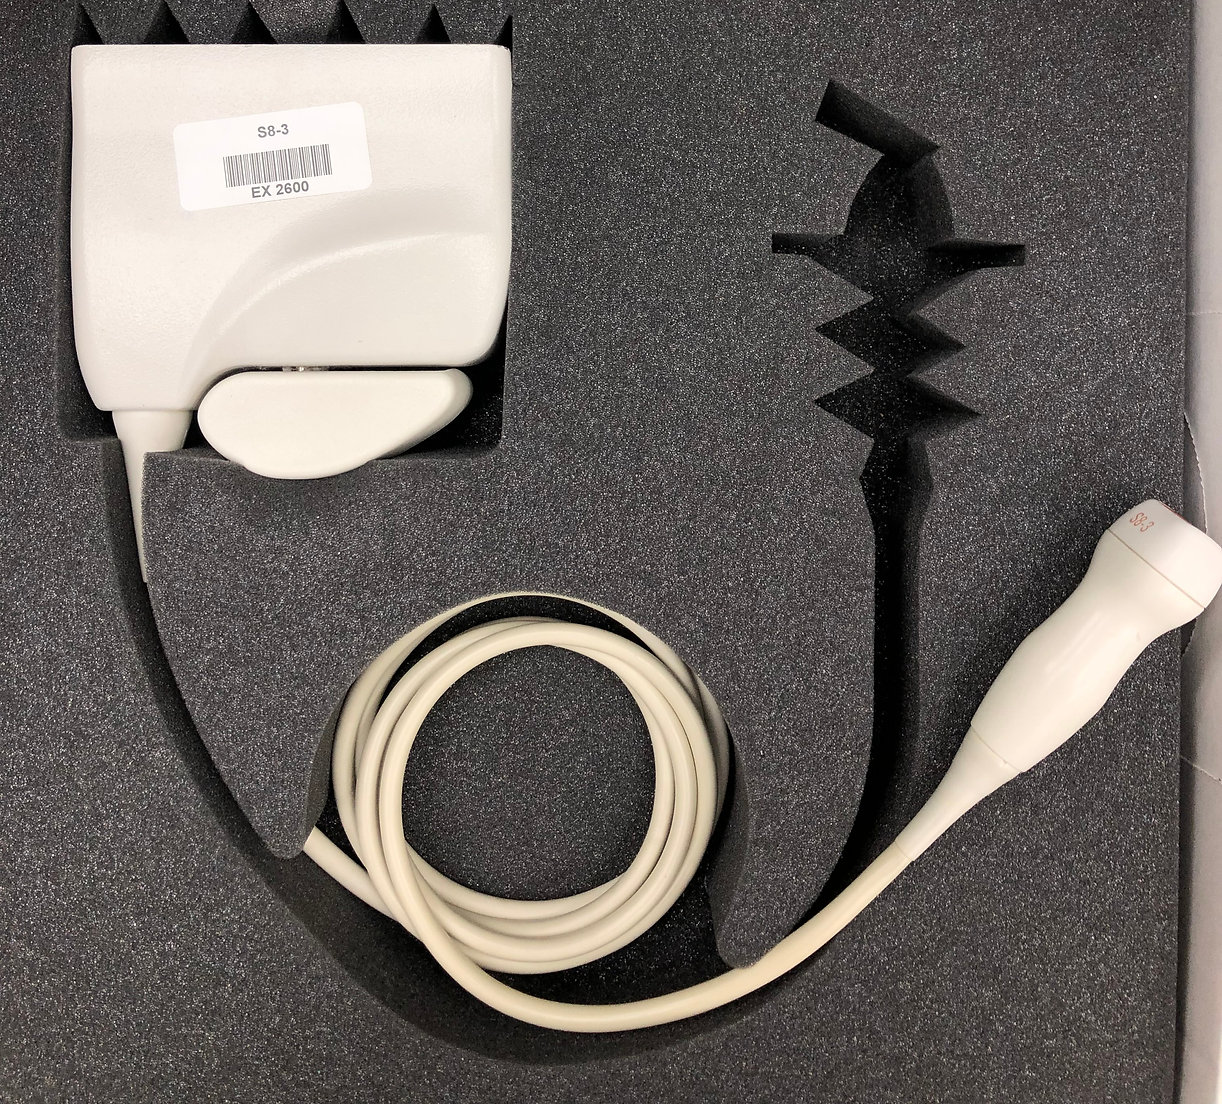

- Transducteur à réseau sectoriel Philips S8-3

- Bande passante : 8-3 MHz

- Champ de vision : 90°

- Applications : applications cardiaques adultes, cardiaques pédiatriques, cardiaques fœtales, abdominales pédiatriques et céphaliques néonatales

- Compatibilité : échographes Philips iE33, HD15, HD11XE et HD11

- Bon état de fonctionnement.